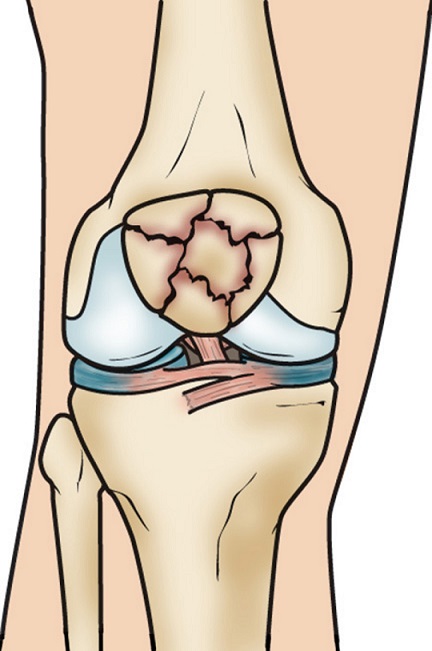

شکستگی مفصل زانو یا در انتهای ران اتفاق می افتد که در قسمت شکستگی های ران شرح داده شد و یا در ابتدای ساق که در همان بخش به توضیح آن خواهیم پرداخت. در اینجا تنها به معرفی شکستگی استخوان کشکک زانو می پردازیم که در جلو زانو قرار گرفته است و تاندون مهمترین عضله ای که موجب حرکت زانو میشود (عضله ی چهارسر ران) به آن متصل می گردد. با انقباض این عضله است که زانو در حالت مستقیم قرار گرفته و انسان توانایی ایستادن پیدا میکند. کشکک در واقع مانند یک سپر و محافظ در جلوی زانو است و ضرباتی که از جلو به زانو وارد میشود را جذب میکند. اگر این ضربات شدید باشند میتوانند موجب شکستگی کشکک شوند. این شکستگی ها حدود یک درصد کل شکستگی های بدن بوده و در مردان دو برابر زنان و بیشتر در سنین بیست تا پنجاه سال دیده میشود.

شکستگی کشکک معمولا به علت ضربه مستقیم مثل زمین خوردن روی زانوی خم شده اتفاق میفتد. در این حالات شکستگی معمولا چند تکه بوده ولی قطعات شکسته شده جابجایی زیادی ندارند .گاهی اوقات انقباض ناگهانی عضله چهارسر ران ممکن است آنقدر شدید باشد که موجب شکسته شدن کشکک شود. در این حالات استخوان کشکک دو تکه میشود و قطعات شکسته شده با یکدیگر فاصله میگیرند .

ممکن است با استفاده از روش های غیر جراحی و یا جراحی انجام شود .در صورتیکه قطعات شکسته شده بدون جابجایی باشند درمان غیر جراحی است. به این صورت که پزشک معالج ابتدا خون داخل زانو را با سرنگ خارج کرده و سپس با استفاده از گچ بلند اندام تحتانی، زانو را یک و نیم ماه در حالت راست و مستقیم نگه داشته تا استخوان های شکسته شده جوش بخورند. اما اگر قطعات شکسته شده از هم جدا شده باشند بیمار نیاز به عمل جراحی دارد به این معنی که پزشک در اطاق عمل پوست را برش میدهد و در زیر آن استخوان شکسته شده کشکک نمایان میشود. جراح سپس قطعات شکسته شده را با ابزارهای بخصوصی در کنار یکدیگر قرار داده و سپس به توسط پین و سیم های فولادی آنها را در کنار یکدیگر محکم میکند.

گاهی اوقات استخوان در محل اتصال به تاندون های بالا و یا پایین خود دچار شکستگی خرد شده و چند تکه میشود. در این حال ممکن است پزشک معالج تکه های خرد شده را پرت داده و تاندون را به قسمت باقیمانده کشکک متصل کند. گاهی وسط کشکک بشدت خرد شده است. در این حالات جراح ممکن است این قطعات ریز و خرد شده را پرت داده و دو قطعه بزرگ و عمده بالا و پایین را به یکدیگر متصل کند . بندرت در شکستگی های بسیار خرد شده کل کشکک، پزشک ارتوپد مجبور میشود تمام قطعات خرد شده یعنی تمام کشکک را پرت داده و تاندون های چهارسر در بالا را به تاندون کشکک در پایین متصل کند .